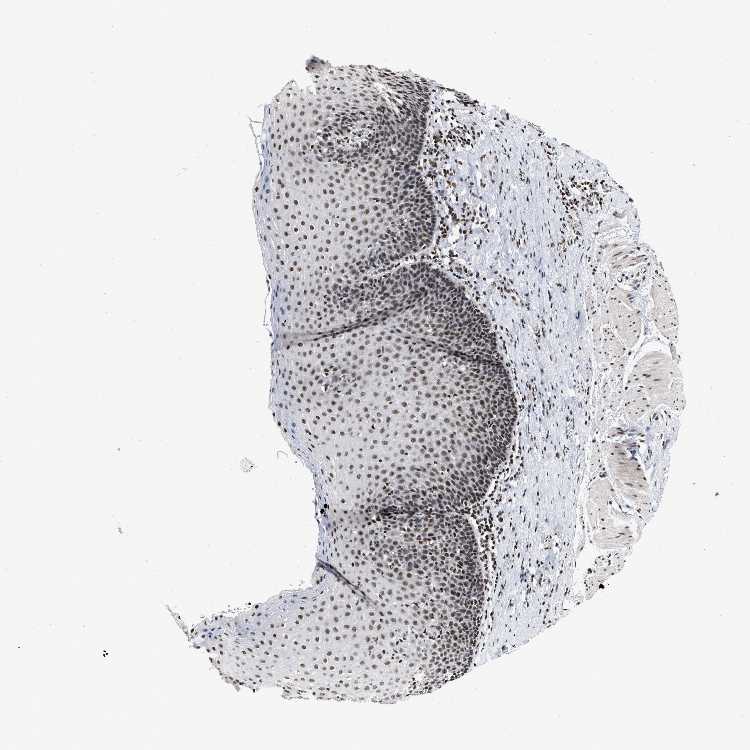

ESOPHAGUS - Antibody stainingi

Antibody staining in the annotated cell types in the current human tissue is reported as not detected, low, medium, or high, based on conventional immunohistochemistry profiling in selected tissues. This score is based on the combination of the staining intensity and fraction of stained cells.

Each image is clickable and will lead to virtual microscopy that enables deeper exploration of all samples and also displays staining intensity scores, fraction scores and subcellular localization as well as patient and tissue information for each sample.

Antibody HPA019150Antibody CAB003803

Squamous epithelial cells HighHigh